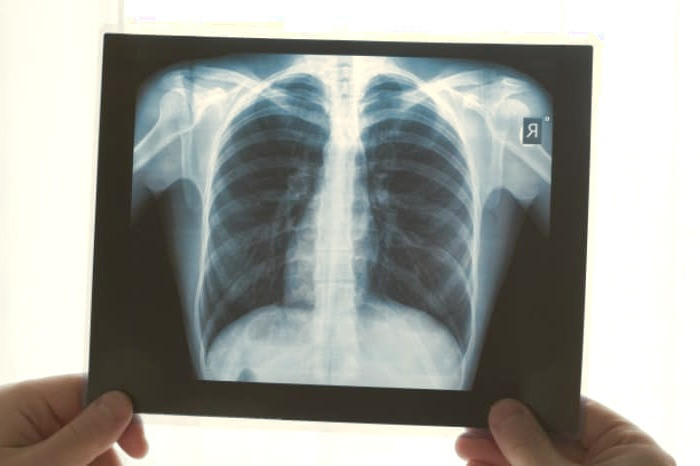

اکثر سرطان هایی که از ریه شروع می شوند، به نام سرطان های ابتدایی ریه، کارسینوماهایی هستند که از بافت پوششی نشات می گیرند. انواع اصلی سرطان ریه سرطان های ریه سلول کوچک (SCLC)، که سرطان سلولی جو شکل نیز نامیده می شود، و سرطان ریه سلول غیر کوچک (NSCLC) هستند. شایع ترین علائم عبارتند از سرفه (همراه با خلط خونی )، کاهش وزن و تنگی نفس.

کسانی که برای مدت طولانی سیگار کشیده اند و بالای 55 سال سن دارند باید اسکن ریه انجام دهند اما دیگر افراد که در این دسته قرار نمی گیرند بهتر است از اسکن ریه ای خودداری نمایند زیرا این نوع از اسکن مقداری تشعشع را به سینه فرد وارد می کند و در برخی موارد نیز به اشتباه نتیجه مثبت اعلام می شود. همچنین مطالعات نشان داده است که استفاده مداوم از میوه ها و سبزیجات تازه به مقدار زیادی خطر ابتلا به سرطان ریه را از شما دور خواهد کرد.